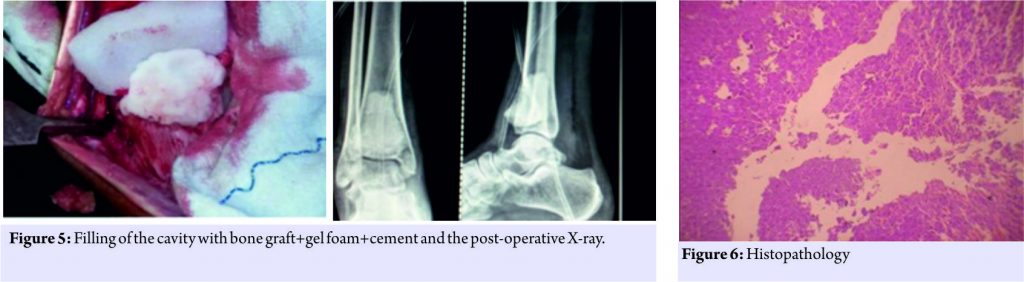

According to the radiological classification of campanacci the tumor was classified as a grade 3 lesions [1]. Laboratory investigations were within normal limits and surgery in the form of intralesional curettage with bone cement was planned. Anterior incision was taken over the distal end of the tibia. Bone was exposed, a cortical window of 3 cm × 2 cm was made (Fig. 3), the tumor was excised (Fig. 4), and curettage was done. The specimen was sent to histopathology for further examination. A thorough wash was given, and the defect was treated with 5% phenol. The cavity was filled with three layers consisting of bone graft, gel foam, and cement mixed with vancomycin, respectively (Fig. 5).

The tumor was sent for histopathological examination which confirmed the diagnosis of GCT (Fig. 6). X-rays were taken at regular follow-up to confirm the union and the cast was removed after 3 months postoperatively, and weight-bearing was started. The patient was followed up regularly with no signs of recurrence.